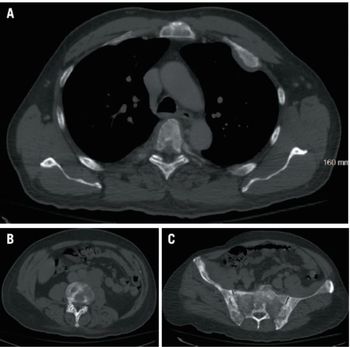

In this case, we examine a 49-year-old man with widespread metastatic sclerotic bone lesions. What is your diagnosis?